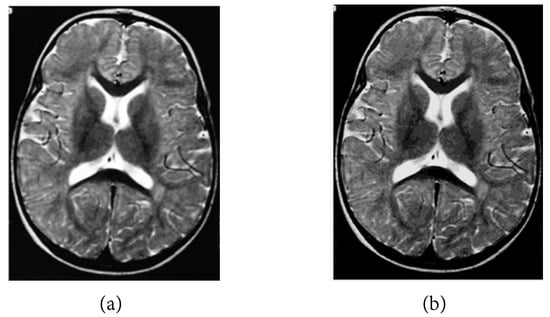

The following numerical results are proposed: Figure 2 presents the original grayscale images for (a) X-ray film of the brain and (b) X-ray film of the right shoulder. Figure 3 and Figure 6 are blurred X-ray films of the brain and the right shoulder images with filtering M i x in the part of degradation of Figure 1. In this example, we set N = 4 . So, we have M 1 x , M 2 x , M 3 x , and M 4 x . Figure 4a, X-ray films of the brain and the right shoulder images were obtained via Theorem 2. Figure 4b, X-ray films of the brain and the right shoulder images were obtained via Theorem 3.1 in [16] (Khuangsatung and Kangtunyakarn’s method). Figure 9 is an X-ray film of the brain image that was recovered via the proposed method that was tuned for the parameter λ.

to measure the quality of recovery; a higher SNR indicates a higher quality of recovery. The following numerical results are proposed: Figure 5 is the SNR results of Figure 4a,b. We see that the SNR of Figure 4a is higher than that of Figure 4b. This means that Figure 4a is better than Figure 4b. Figure 8 is the SNR results of Figure 7a,b. We also see that the SNR of Figure 7a is higher than that of Figure 7b. This means that Figure 7a is better than Figure 7b. Figure 10 is the SNR of Figure 9 when we select a higher λ value inside the specified range to produce a higher quality image than a lower λ value.

Figure 9. X-ray film of the brain image obtained via Theorem 2 when Example 1 was tuned for the parameter λ by setting (a) λ = 0.25, (b) λ = 0.5, (c) λ = 0.75, (d) λ = 1.